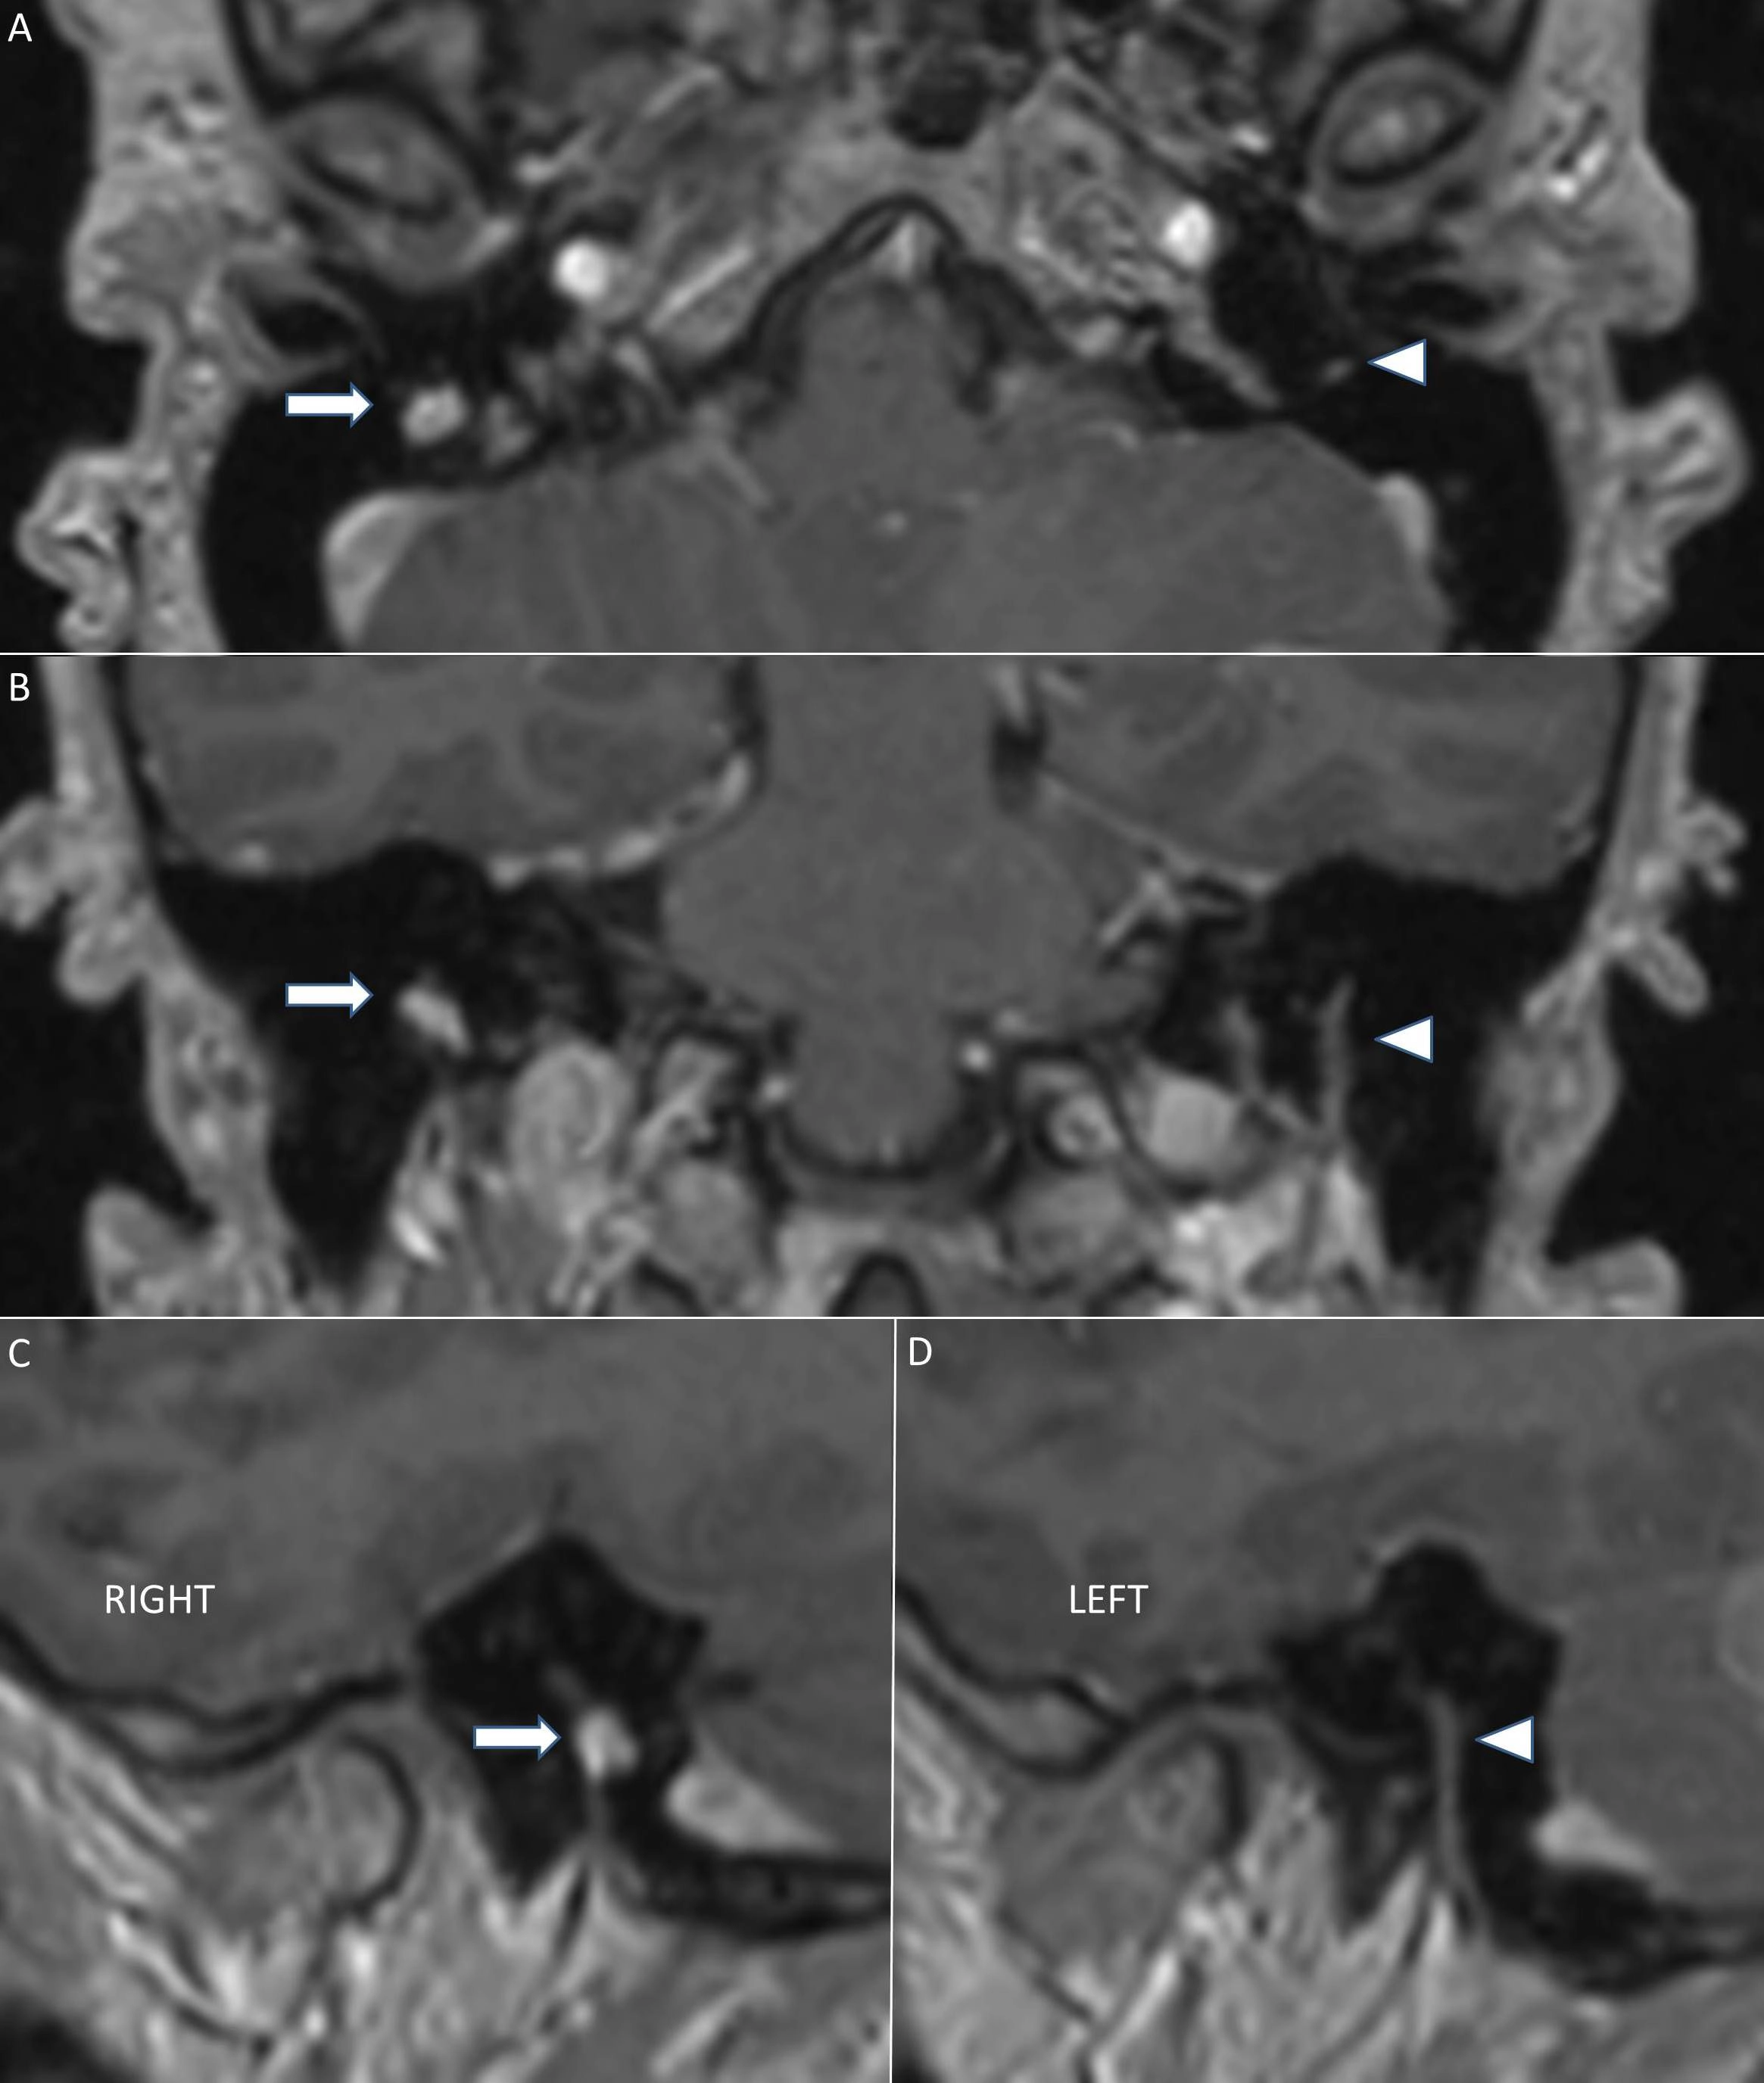

• U bao dây thần kinh tiền đình (Vestibular schwannoma - VS)

• Phân loại Koos cho u schwannoma tiền đình - Koos classification of vestibular schwannomas